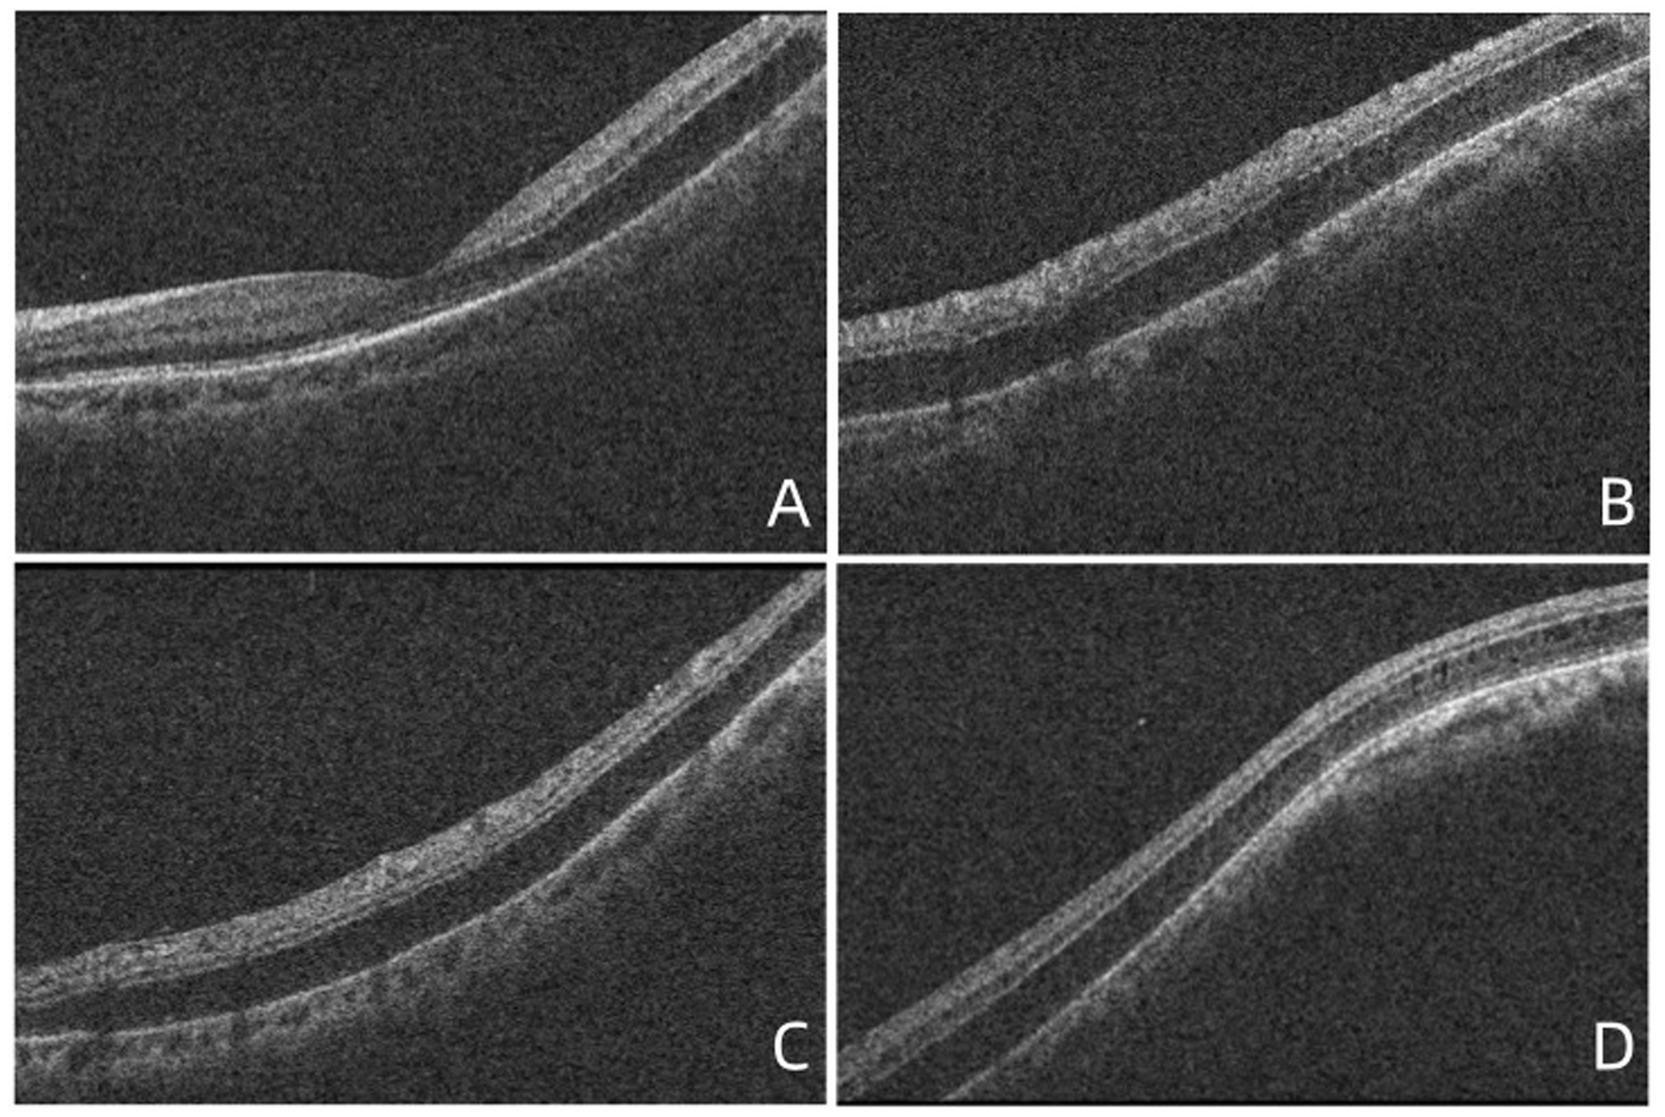

At the time of the patient’s visit, the axial length was 25.33 mm in the right eye and 25.16 mm in the left eye; his axial length 1 month ago was 25.24 mm in the right eye and 25.14 mm in the left eye. There was no significant difference in axial length between them. The corneal curvatures of the right and left eyes were 44.00 and 43.25 D, respectively. Anterior segment examination was normal, and no inflammatory cells were observed in the anterior chamber or vitreous of the left eye. B-ultrasonography revealed no vitreoretinal traction. Optical coherence tomography (OCT) demonstrated retinal splitting in the macular area, on the temporal side of the macula, and near the superior and inferior vascular arches, occurring in the outer plexiform layer without a macular hole, VMT, or macular epiretinal membrane (ERM) (Figure 1). Fluorescein and indocyanine green angiography revealed no capillary leakage in the macula or optic disc (Figure 2). There were no obvious abnormalities in the binocular visual field. Although no active inflammation was present in the left eye, the patient was given empirical therapy including oral prednisolone at 60 mg/day for 1 week, followed by 50 mg/day for 1 week. Steroid eye drops were prescribed as well. After this 2-week treatment, OCT showed that the retinoschisis had become aggravated, and the best-corrected visual acuity had decreased to 20/66 (Figures 3A,B and Figures 4A,B,E,F,I,J).

Figure 3. (A,B) OCT demonstrated that foveoschisis was aggravated 2 weeks after the patient was diagnosed and the foveoschisis cavity was expanded, and the best-corrected visual acuity (BCVA) decreased to 20/66. (C) Twenty-seven days after diagnosis, the OCT demonstrated that there was no obvious improvement in foveoschisis. (D) Forty days after diagnosis, the foveoschisis began to improve significantly; the volume of the cavity was significantly reduced. (E) Fifty-five days after diagnosis, the retinoschisis in the macula had resolved completely in the OCT appearance, with BCVA recovering to 20/33.

The patient visited our hospital again after returning from Beijing (27 days after diagnosis). OCT demonstrated that there was no obvious improvement in the foveoschisis (Figure 3C); however, the retinoschisis near the inferior (Figure 4C), superior (Figure 4G) vascular arches and the temporal of macula (Figure 4K) had begun to improve. The prednisolone was reduced to 30 mg/day and then reduced by 10 mg every 3 days. Forty days after diagnosis, the foveoschisis began to markedly improve (Figure 3D), and the retinoschisis near the inferior (Figure 4D) and superior (Figure 4H)vascular arches and the temporal side of the macula (Figure 4L) had completely resolved. Fifty-five days after diagnosis, OCT showed that the retinoschisis in the macular region had also completely resolved, with the best-corrected visual acuity recovering to 20/33 (Figure 3E). After a follow-up observation of 14 months, the vision of his left eye was stable, and macular OCT indicated that the structure of each layer of the retina was normal.

Figure 4. (A–D) OCT demonstrated that no significant improvement in retinoschisis near the inferior vascular arch 2 weeks after diagnosis, 27 days after diagnosis, the retinoschisis cavity was reduced, 40 days after diagnosis, the retinoschisis had completely resolved. (E–H) OCT demonstrated that no significant improvement in retinoschisis near the superior vascular arch 2 weeks after diagnosis, 27 days after diagnosis, the retinoschisis cavity was reduced, 40 days after diagnosis, the retinoschisis had completely resolved. (I–L) OCT demonstrated that no significant improvement in retinoschisis near the temporal side of the macula 2 weeks after diagnosis, 27 days after diagnosis, the retinoschisis cavity was reduced, 40 days after diagnosis, the retinoschisis had completely resolved.